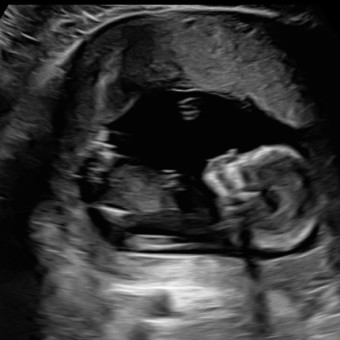

Thank you so much for celebrating our baby Ariana Giannina with us 🤍 We’ve included a mix of essentials, keepsakes, and funds so you can choose what feels right for you.